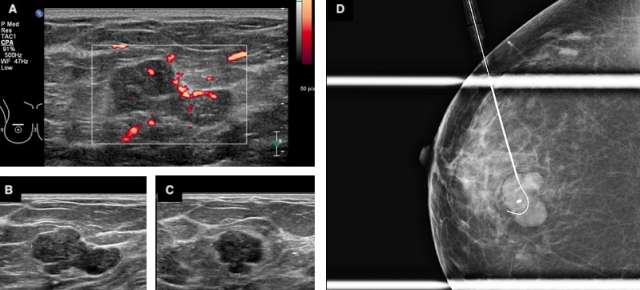

Figure 2. A 53-year old female presents with a palpable abnormality in the right breast 12:00 position 4 centimeters from the nipple. Targeted sonography (A-C) reveals an irregular hypervascular mass with microlobulated margins measuring 2.7 x 1.6 x 1.4 cm. A biopsy was performed with a pathologic diagnosis of a “cellular fibroepithelial lesion”. Patient was referred for surgical consultation. Wire localization of the mass was performed of the irregular mass (C) prior to lumpectomy. Final pathologic diagnosis revealed phyllodes tumor.